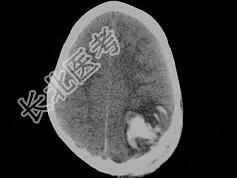

- 单项选择题男,3岁, 头颅被球击中,请结合CT图像, 选择最可能的诊断是  (    )

A、高血压性脑出血

B、脑结核

C、脑挫裂伤血肿形成

D、动脉瘤破裂出血

E、血管畸形